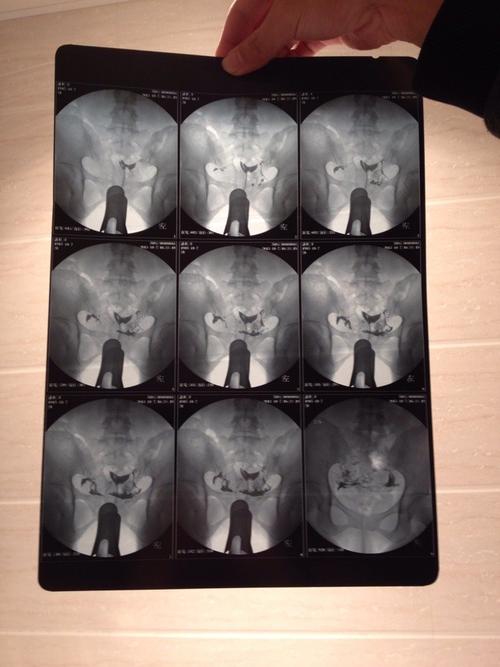

输卵管不通畅会怀孕吗

输卵管不通畅是现代不孕女性经常遇到的一个原因,有人说是输卵管不通畅的原因,那么输卵管不通畅真的会怀孕吗?我们一起来了解一下。